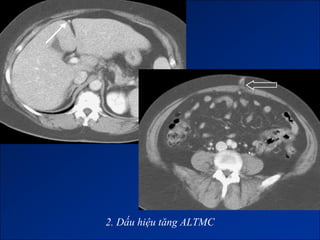

2. Dấu hiệu tăng ALTMC